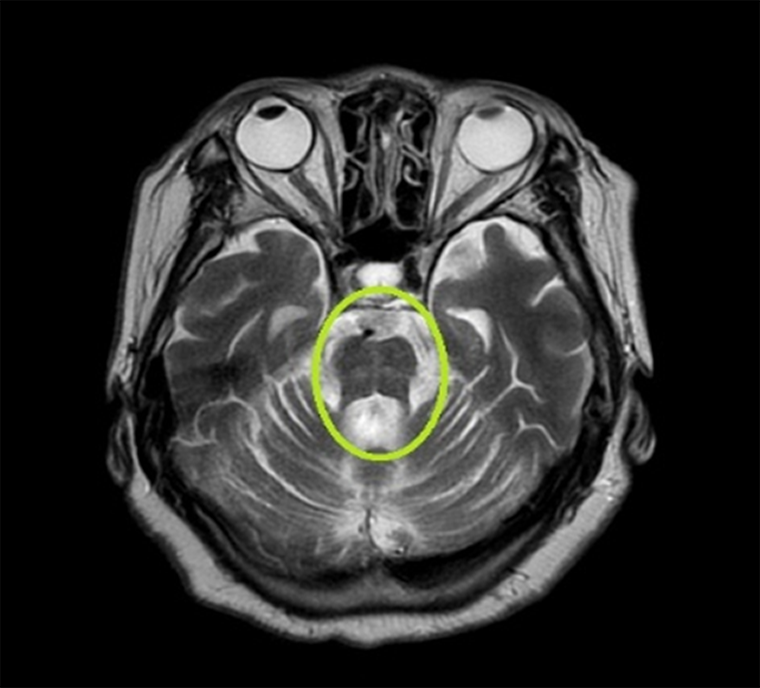

有鑒於此,醫療團隊特別安排個案接受躺、坐、站時不同血壓檢查,發現收縮壓值由臥姿改變至站姿後,竟下降超過40毫米水銀柱且同時出現頭昏感,遠大於一般人血壓下降不超過20毫米水銀柱的範圍。同時病患的腦部核磁共振影像也發現,腦幹異常萎縮與出現獨特的熱十字麵包徵候(Hot cross bun sign),綜合上述臨床症狀表現後,醫師懷疑是罹患多發性系統萎縮症(MSA)。

▲黃阿嬤的腦部MRI影像出現腦幹異常萎縮,及獨特的「熱十字麵包徵候」異象。(圖/亞洲大學附屬醫院提供)